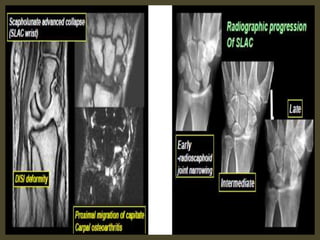

A simple approach is to consider the lunate

which is usually the easiest carpal bone to

visualize on a lateral wrist image. If the

lunate is abnormally tilted in a dorsal

direction on a standard lateral wrist image,

a DISI should be considered. If the lunate is

abnormally tilted in a volar direction a VISI

should be considered. DISI is due to

disruption of the scapho-lunate articulation.

VISI is secondary to disruption of the luno-

triquetral articulation.

DISI deformity.

DISI.